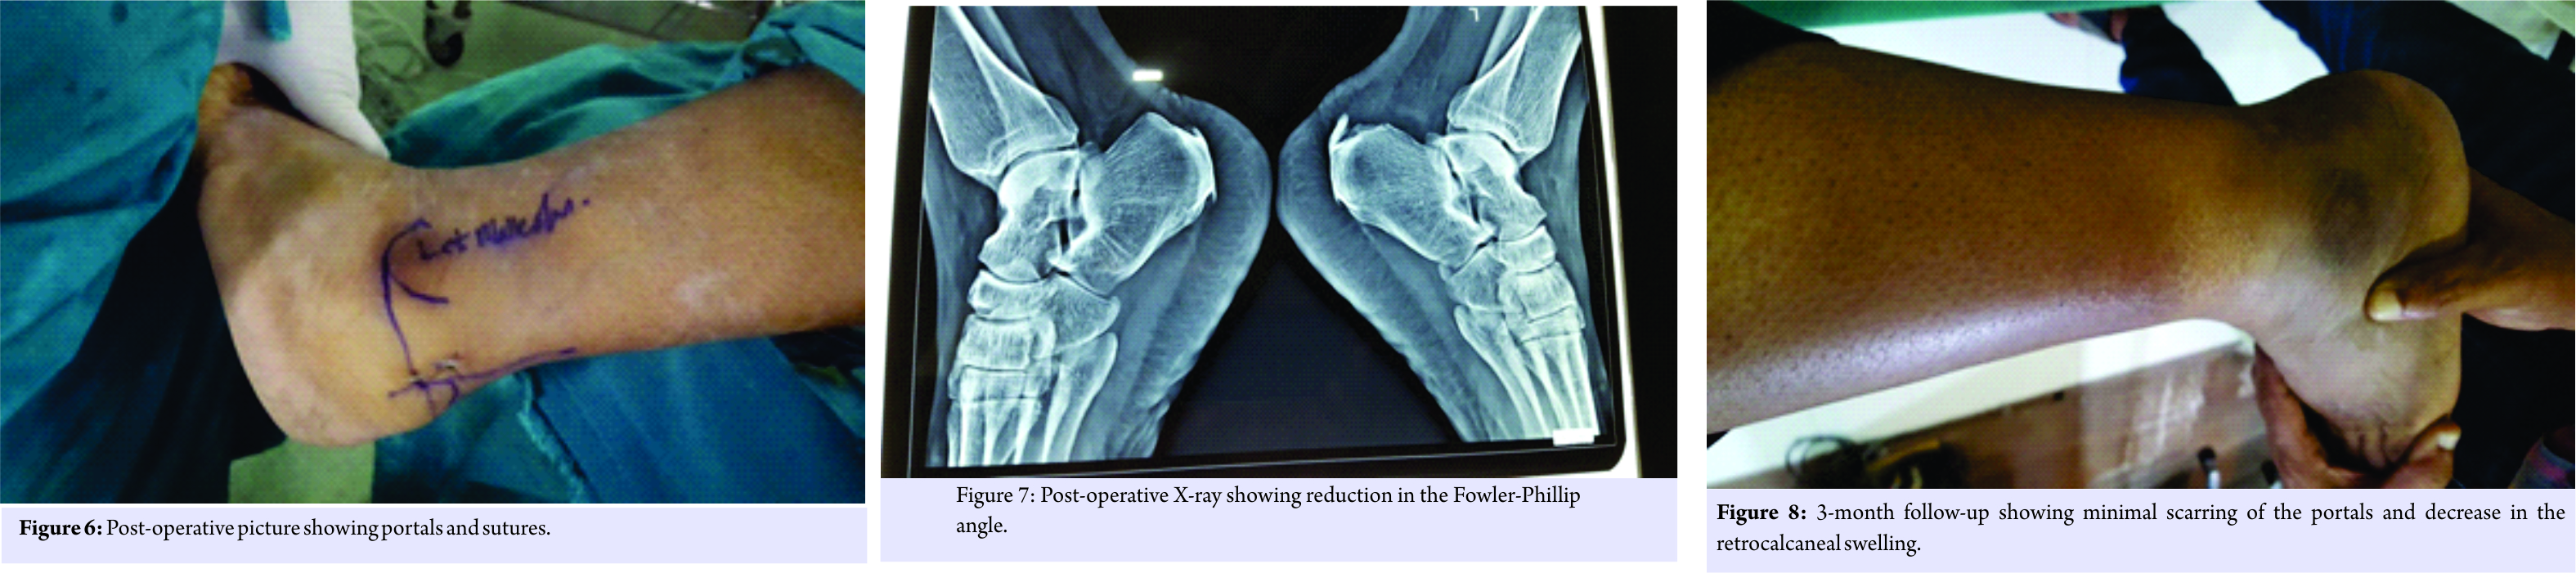

Then, an accessory lateral portal is created by giving a stab incision below the posterolateral portal using a needle as a guide so as to reach the posterolateral corner of the calcaneum. A stab incision is given, spread with mosquito forceps while entering the retrocalcaneal space. The bursa is shaved with a shaver tip facing away from the Achilles tendon. The medial and lateral corners of the Haglund’s bump are viewed after the bursa is shaved off. An osteotome is passed through the accessory lateral portal (Fig. 3) and the Haglund’s bump is removed and is confirmed on fluoroscopy and by plantar flexing the ankle to see whether the sufficient amount has been removed or not. The sharp edges are smoothened using an acromioniser (Fig. 4 and 5). The skin is closed using non-absorbable sutures, and pressure dressing is applied, tourniquet is released (Fig. 6).

The patient started full ankle range of movements and weight-bearing as tolerated from the 1st post-operative day (P.O.D). He was discharged on the 2nd P.O.D after primary dressing and suture removal was done on the 12th P.O.D. Patient started full weight-bearing from the 13th P.O.D. His post-operative X-ray showed reduction in Fowler-Phillip angle from 71 to 45 (Fig. 7). We did not encounter any complications during intraoperative and post-operative follow-up period. He was followed on the 1st, 3rd, and 6 months postoperation and his AOFAS score improved from 64 to 98 at 6-month follow up. Patient is pleased as there was no swelling in the retrocalcaneal region with minimal scar tissue formation (Fig. 8) and early rehabilitation.